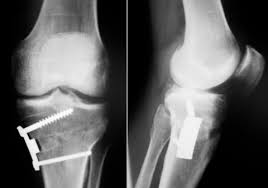

Filme De Raios X De Um Joelho De Um Paciente Com Tibia Proximal Fraturada Apos A Fixacao Da Placa E Dos Parafusos Foto Premium

Tibia Proximal Da Fratura Da Articulacao Do Joelho Do Raio X E De Reparo Do Cargo Tibia Proximal Da Fratura Imagem De Stock Imagem De Ferimento Ciencia 134286017

Raio X Articulacao Do Joelho Fratura Da Tibia Proximal E Fratura Pos Tibia Proximal Da Tibia Foto Premium